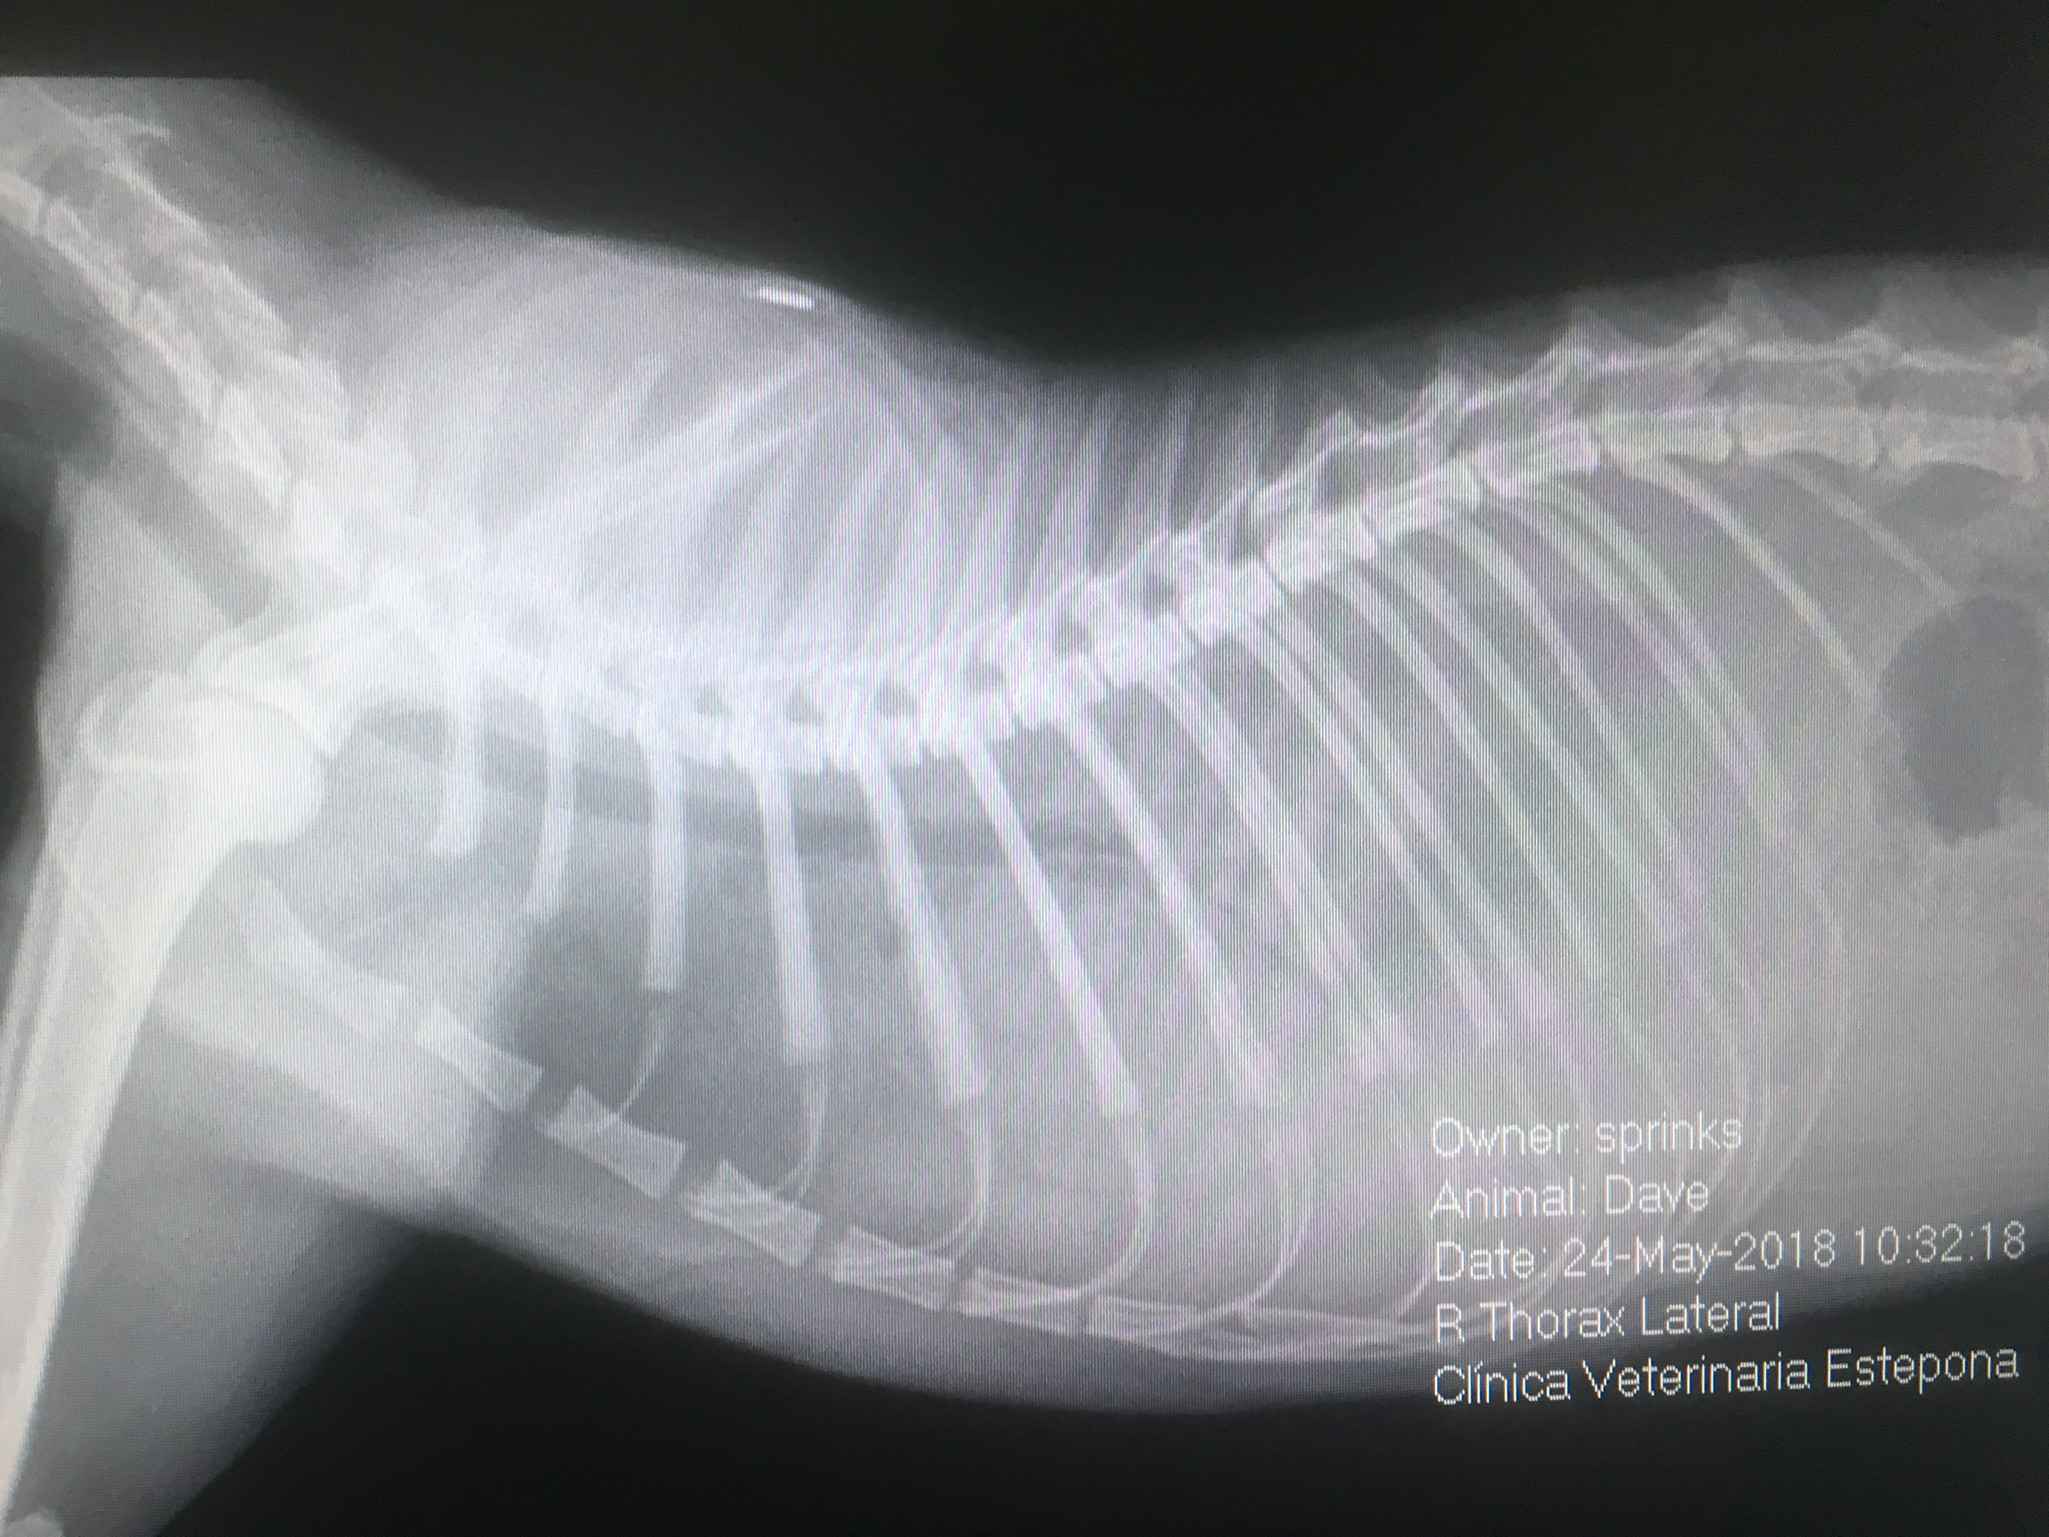

С другой стороны, радиология очень полезна для диагностики костной, брюшной и грудной патологий. В Ветеринарной Клинике Эстепона мы полагаемся не только на классическую радиологию, но и на контрастную радиологию, поэтому можно проводить специализированные рентгенологические исследования, такие как миелография (для диагностики патологий спинного мозга), урография и позитивная контрастная цистография. двойной контраст (для диагностики проблем с почками и мочеиспусканием) и контрастного исследования пищеварительного тракта (для желудочно-кишечных проблем) и другие.